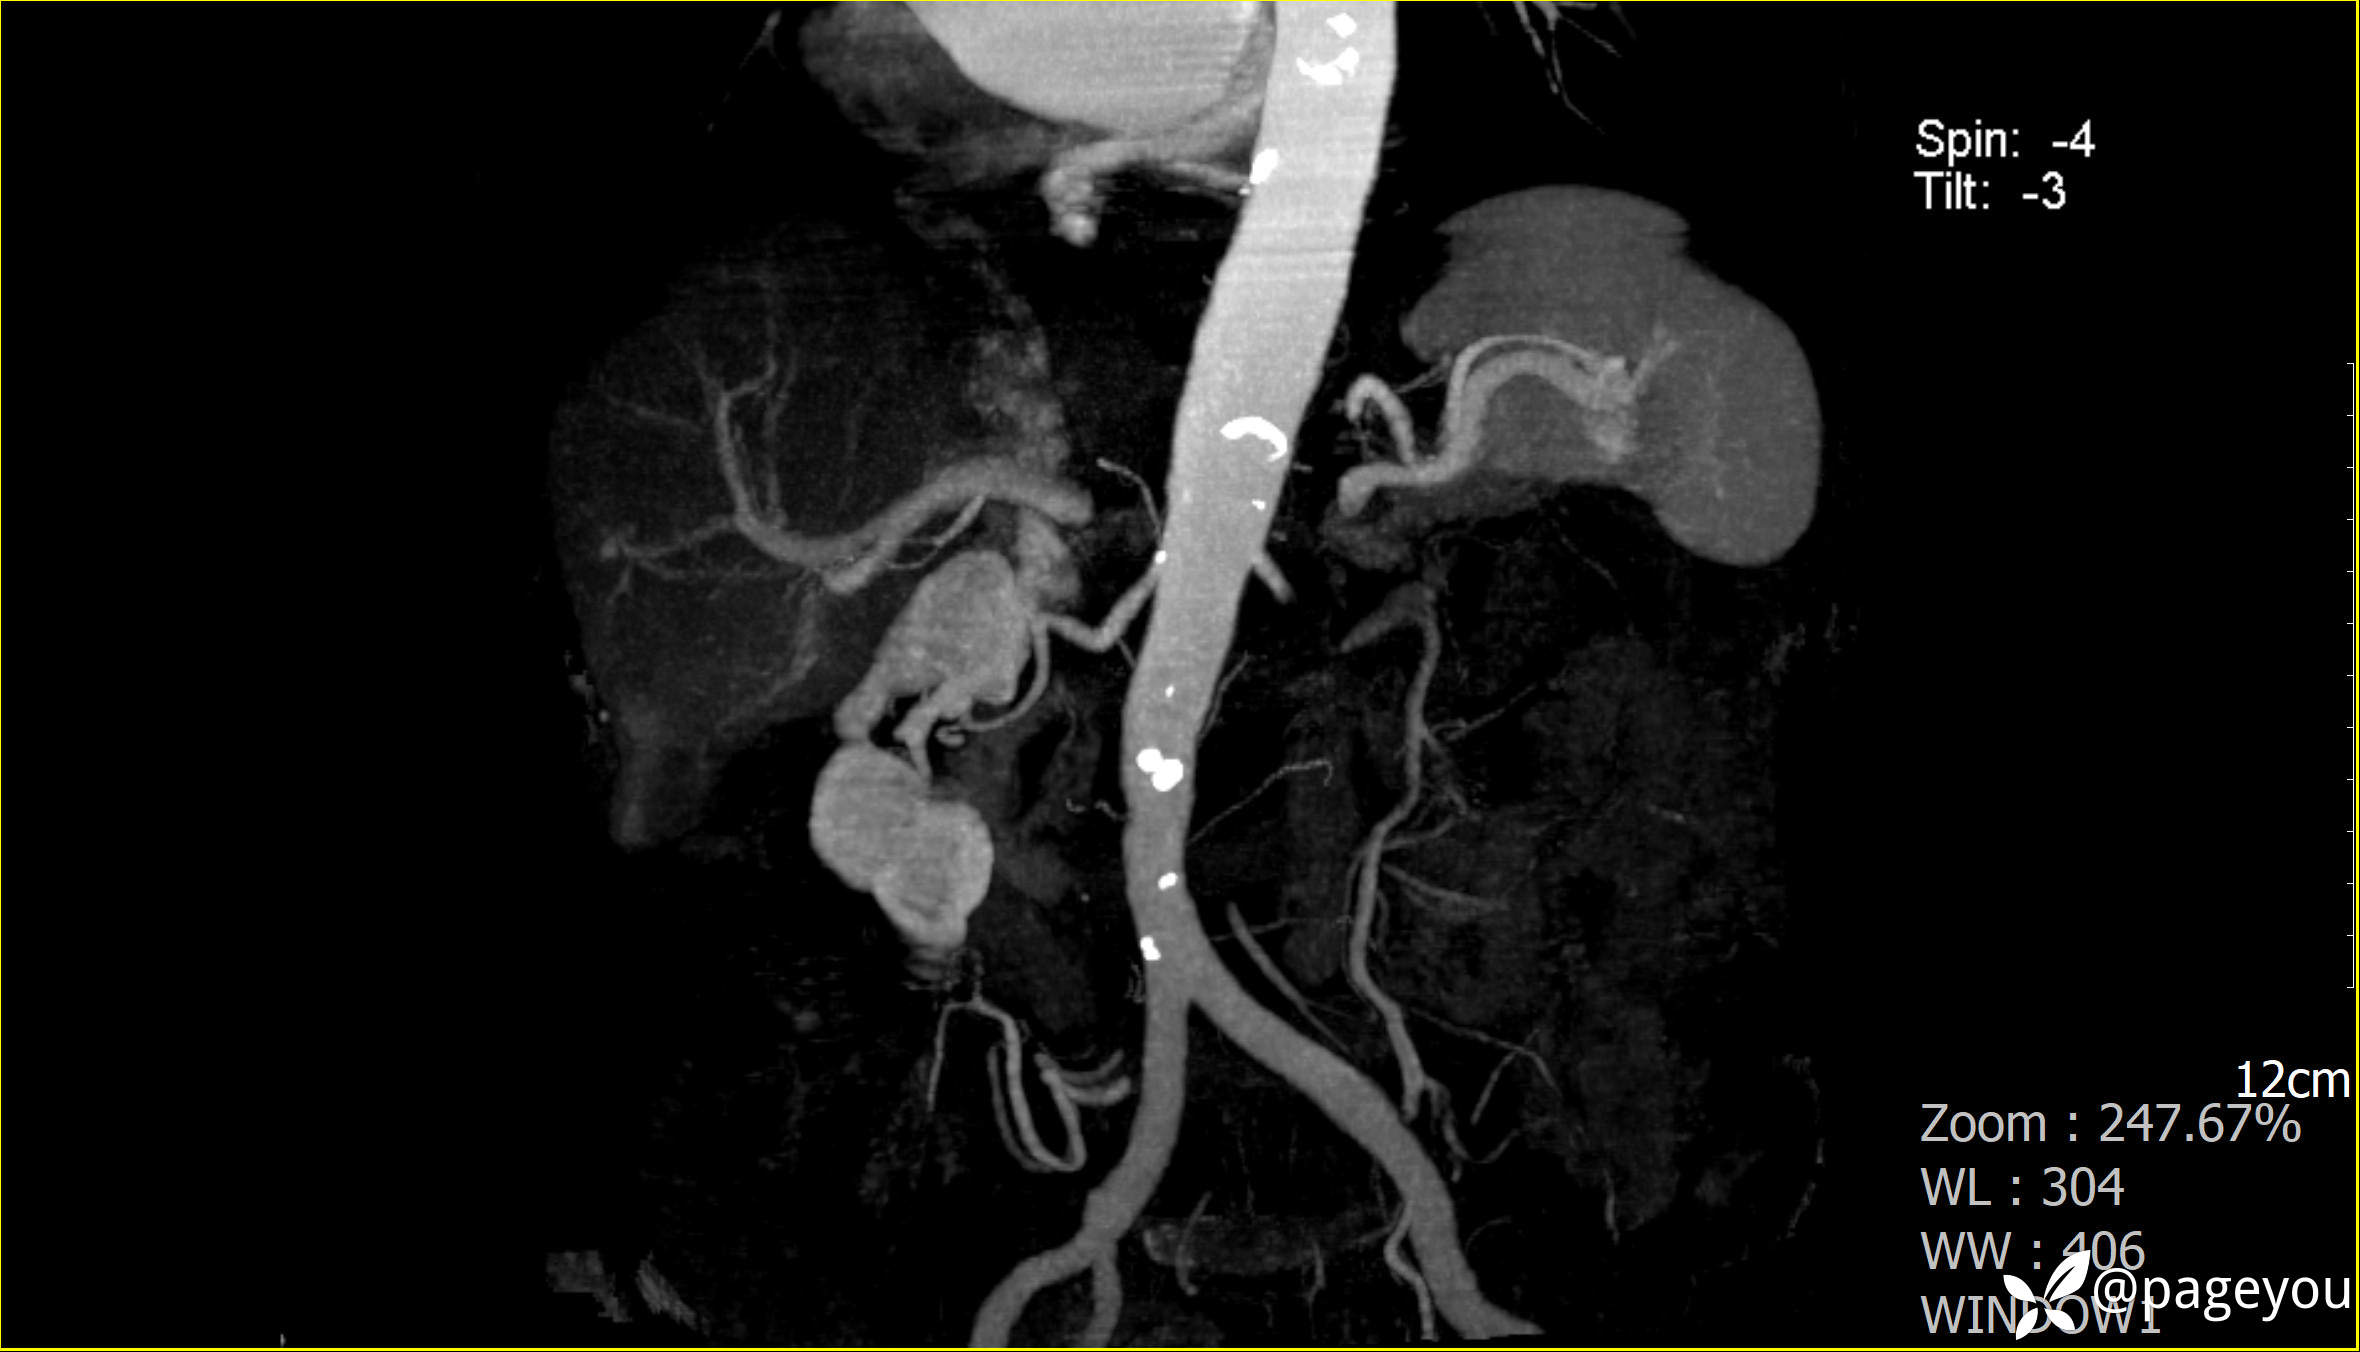

主动脉CTA: